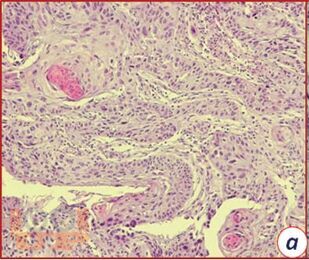

В пособии разобраны вопросы эндоскопической и морфологической диагностики рака пищевода, приведены статистические данные и современные классификации, рассмотрена клиническая картина заболевания. На конкретных примерах ракового поражения пищевода с фотографиями даны варианты протокола эндоскопического заключения. В приложениях собраны эндоскопические классификации рака пищевода, в том числе Японская классификация (2017).